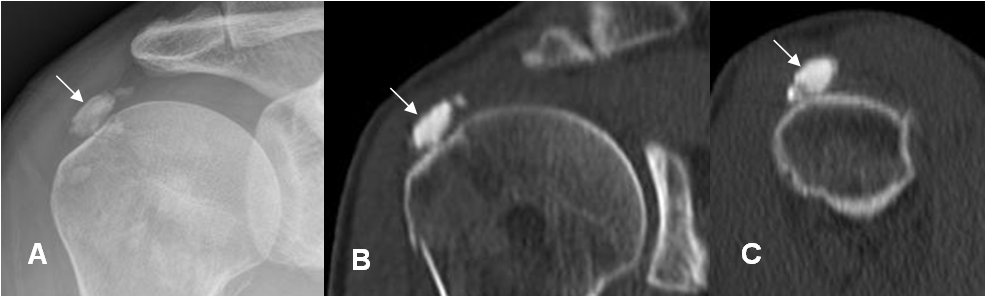

Fig 140 A. Tendinitis calcificada.

A: Rx AP, B: TAC reconstrucción coronal y C: TAC reconstrucción sagital. Imagen ovalada y densa, en el tendón del supraespinoso, que corresponde a tendinitis calcificada.